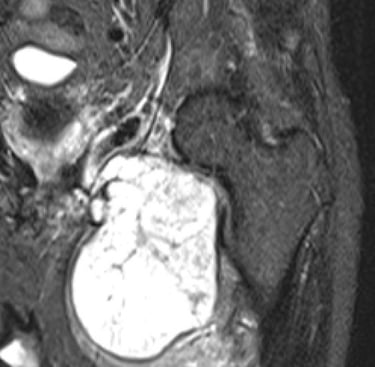

This is the second most common type of primary bone cancer, particularly over the age of 40. It often develops from normal cartilage cells or may occur in patients with pre-existing benign cartilage tumours eg. enchondromas, multiple osteochondromas, Ollier or Maffucci syndrome. Most occur in the femur, humerus, pelvis and around the knee but can occur in any bone. Most patients are treated with surgery alone as these are generally not responsive to chemotherapy or radiotherapy.

Diagnosis of chondrosarcoma can be very challenging. These can range from low grade (grade1) to high grade (dedifferentiated) and diagnosis often require a number of tests. Biopsies are often not recommended as these tumours are difficult to differentiate histologically. Diagnosis is generally made clinically and radiologically.